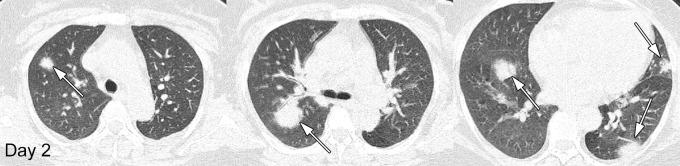

Longitudinal CT Findings in COVID-19 Pneumonia: Case Presenting Organizing Pneumonia Pattern.

Radiol Cardiothorac Imaging. 2020 Feb 14;2(1):e200031. doi: 10.1148/ryct.2020200031. eCollection 2020 Feb.